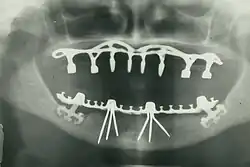

Панорамная рентгенограмма исторических дентальных имплантатов, сделанная в 1978 г.